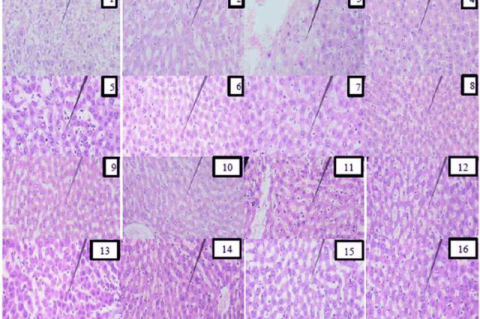

Histopathological micrographs of rat liver sections Arrows indicate areas of hepatocellular degeneration characterized by cytoplasmic vacuolization and disrupted hepatic cord architecture.